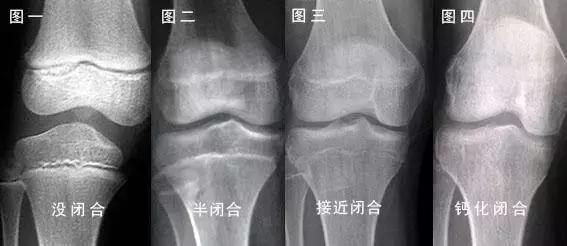

普及下人类长高的关键,在是一个叫做「骨骺」的部位。

骨骺就像腿骨上的盖子,一旦闭合,人也就没法长高了。

一般来说,股骨上端的骨骺闭合最早,约在 16~18 岁左右;股骨下端和胫骨上端的骨骺闭合晚,约在 19~24 岁左右。

人能否长高和是否成年没有绝对的对应关系,只和骨骺是否闭合有对应关系。